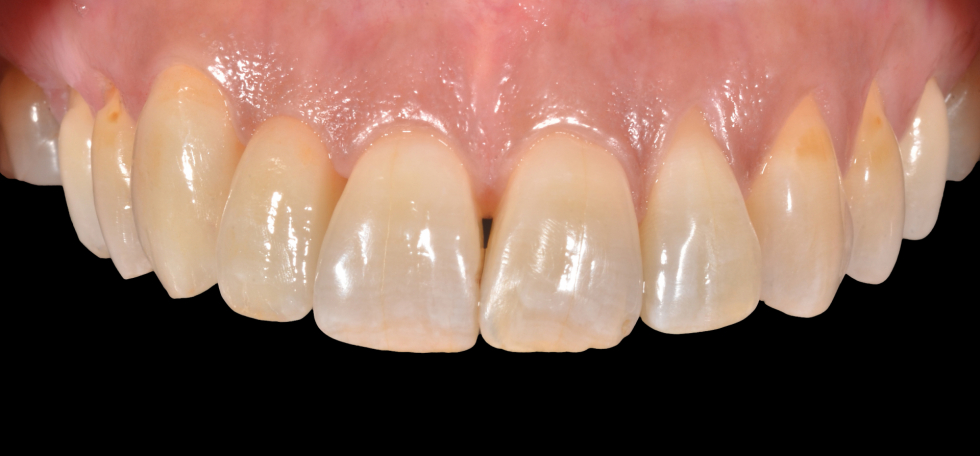

miglioramento estetico di un dente su impianto

un caso emblematico dove un impianto sostituisce la perdita di un dente. Qui l'intervento di innesto gengivale e una dente di forma e colore sbagliati hanno creato un inestetismo che impedisce alla paziente di sorridere

il sorriso prima delle terapie

evidente anomalia della forma del dente e la tumefazione della gengiva dovuta ad un intervento di chirurgia

modificando la forma del dente con il provvisorio si ottiene già un primo rimodellamento della gengiva

il moncone avvitato sull'impianto

corona definitiva in ceramica